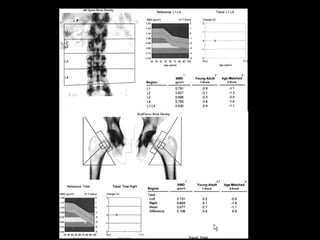

Bone densitometryBone densitometry; gold standard

1. Detection osteoporosis before fractures.

2. Determination disease severity.

3. Estimation risk of fracture.

– Serial BMD measurements enable determination

of rate of bone loss or gain and thereby help in

monitoring therapy.